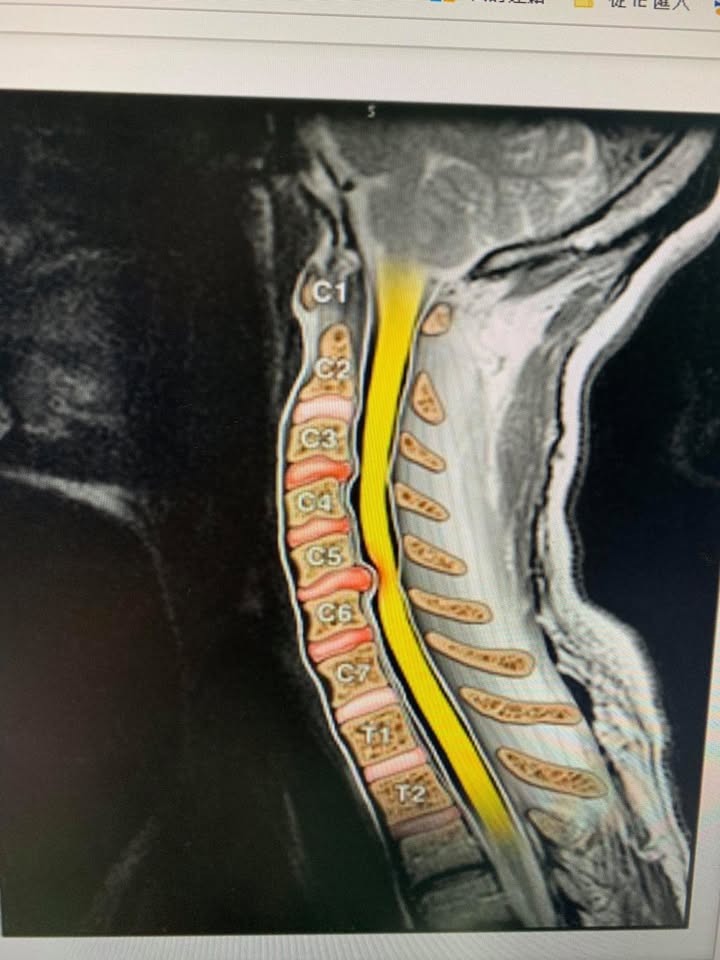

😂😂年過花甲的林大哥抱怨左邊頸痛連肩膀,最近這三個月明顯惡化,頭往後馬上有麻電感,之前長期需要低頭打字密集使用頸部肌肉群,一開始只是肩膀痠痛,後來最近發現整條手臂就開始麻痛才覺得不對勁,去台北榮總醫學中心接受頸椎mri核磁共振照影顯示頸椎第四第五輕微突出導致神經根卡壓(如圖),醫師建議如果復健效果不好則可能要接受頸椎人工關節墊片置換術,經過友人介紹接受頸椎整合中醫微創療法,非常幸運六次效果就很明顯,這幾次去爬山跟日常生活動作發現手的麻痛感大幅度降低,非常開心,這次治療好徐醫師提醒頸部跟肩膀肌肉要適時放鬆跟強化頸部深層肌肉的力量才不會再度復發

🔷通常為單根神經根受累,也可由多節段病變致兩根或多根神經根受壓。頸椎病變主要見於頸4~5以下,以頸5、頸6與頸7神經根受累最為多見。